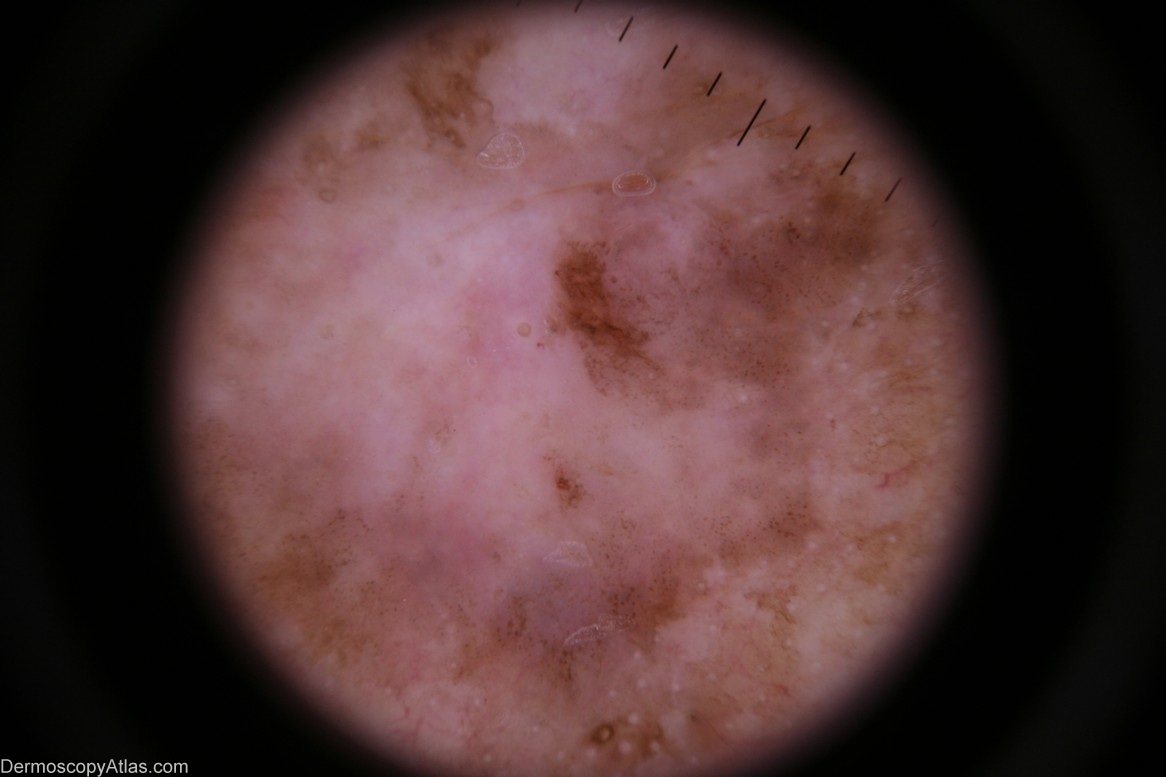

Image Number #2700 (Pigmented Intraepidermal carcinoma)

Diagnosis: Pigmented Intraepidermal carcinoma

Description: Dermoscopy - There is no pigment network nor are there any other melanocytic features.The distribution of the pigment is asymmetrical. There are milky-red areas and aggregated brown dots. The white circular structures may be milia-like cysts in the adjacent seborrhoeic keratosis which was reported on histology.

History: This lesion was encountered at a routine skin check at the same time as a level 1 melanoma was discovered on his scalp (image 260 in this atlas). Shave biopsy was reported as "...pigmented intraepidermal carcinoma". The definitive excision was reported as "...pigmented intraepidermal carcinoma and seborrhoeic keratosis". IEC,s do sometimes arise in pre-existing seborrhoeic keratoses. This may be the case here or the two lesions may be separate and in collision. The skin on this man's back was severely sun-damaged.